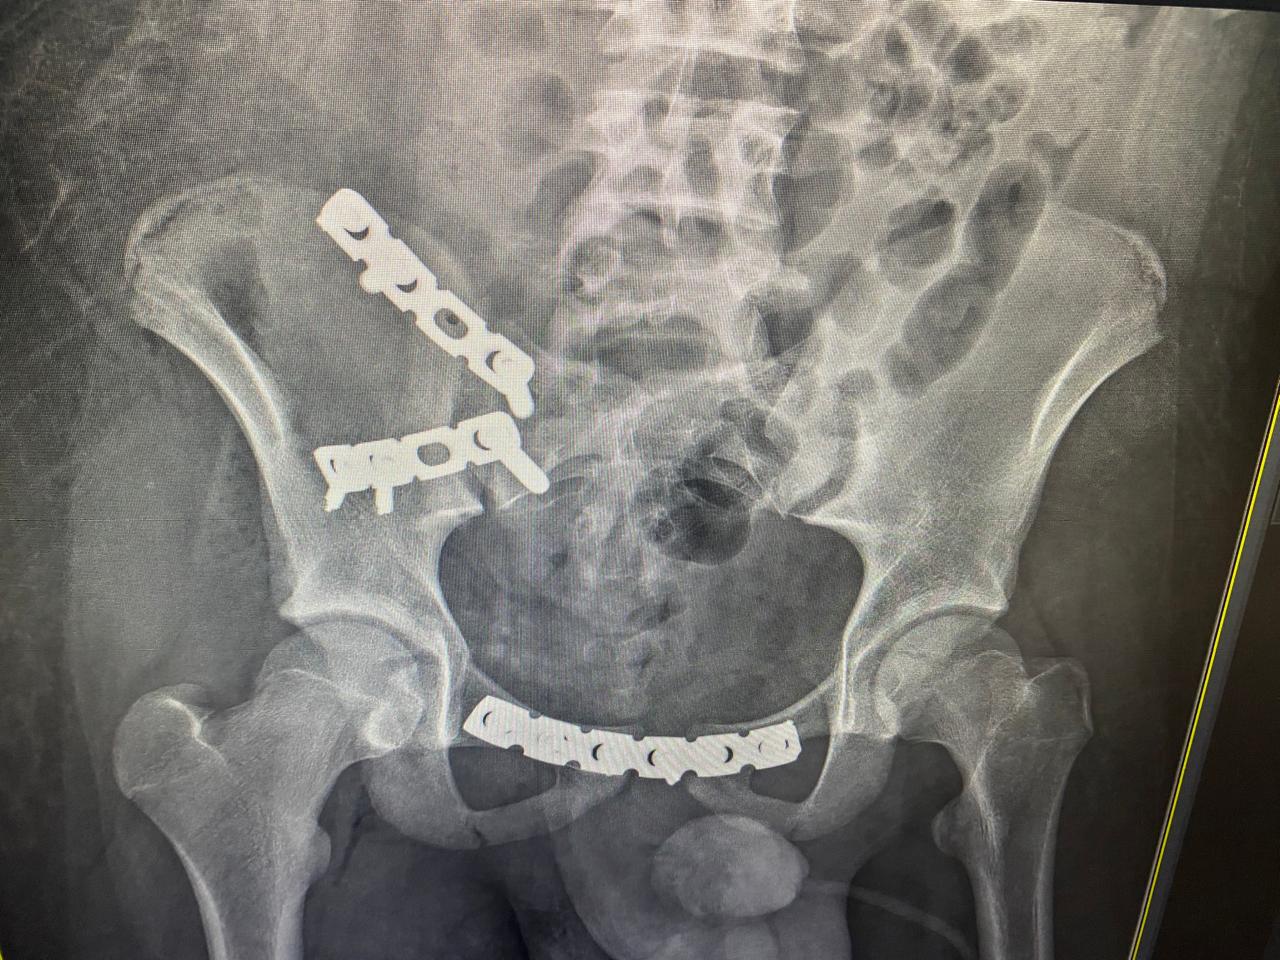

ياسين محمد أمين العمر:١٧ عامًا اصيب بكسر غير ثابت متفتت بالحوض يناير ٢٠٢٣